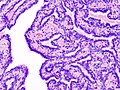

Intraductal papilloma. H&E stain. | |

| LM | true papillae (nipple-shaped structures with fibrovascular cores), intraductal proliferation of epithelial and myoepithelial elements, +/-hyalinization |

- True papillae - nipple-shaped structures with fibrovascular cores.

- Intraductal proliferation of epithelial and myoepithelial elements.[3]

- Lacks florid hyperplasia.[4]

- May degeneration and hyalinize to form a sclerosing papilloma.